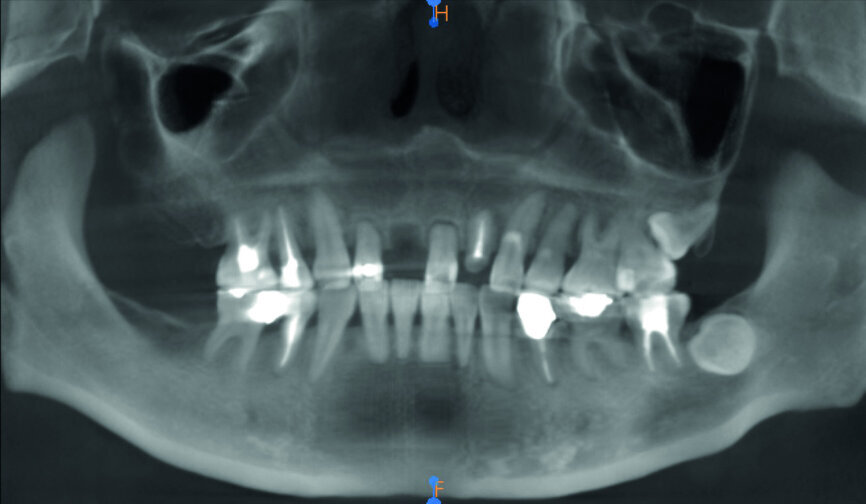

Fig. 3: Pre-op panoramic radiograph.

A 40-year-old female patient had sustained trauma to her anterior teeth caused by accidental syncope three weeks before. The clinical examination found that tooth #11 had been luxated; the crowns of teeth #12 and 21 had fractured, with the residual margin extending 3–5 mm below the gingiva and the teeth affected by Grade III mobility; and the crown of tooth #22 had fractured, with the residual margin at gingival level. There were no obvious abnormalities in the remaining teeth (Figs. 1–4). After excluding major systemic diseases, it was decided that she required fixed implant restoration with high demands regarding aesthetics and function.

Three weeks later, after a general physical check-up, implantation was begun. Usually, operation within 48 hours after tooth extraction is considered as immediate implantation, while operation within the first six weeks after tooth extraction is considered as early implantation. Therefore, in this case, implant #11 was early implantation and implant #22 immediate implantation. The preoperative CT analysis showed that the labial side of the alveolar ridge of teeth #12, 11 and 22 was deficient; thus, GBR was needed in order to obtain sufficient bone quantity.